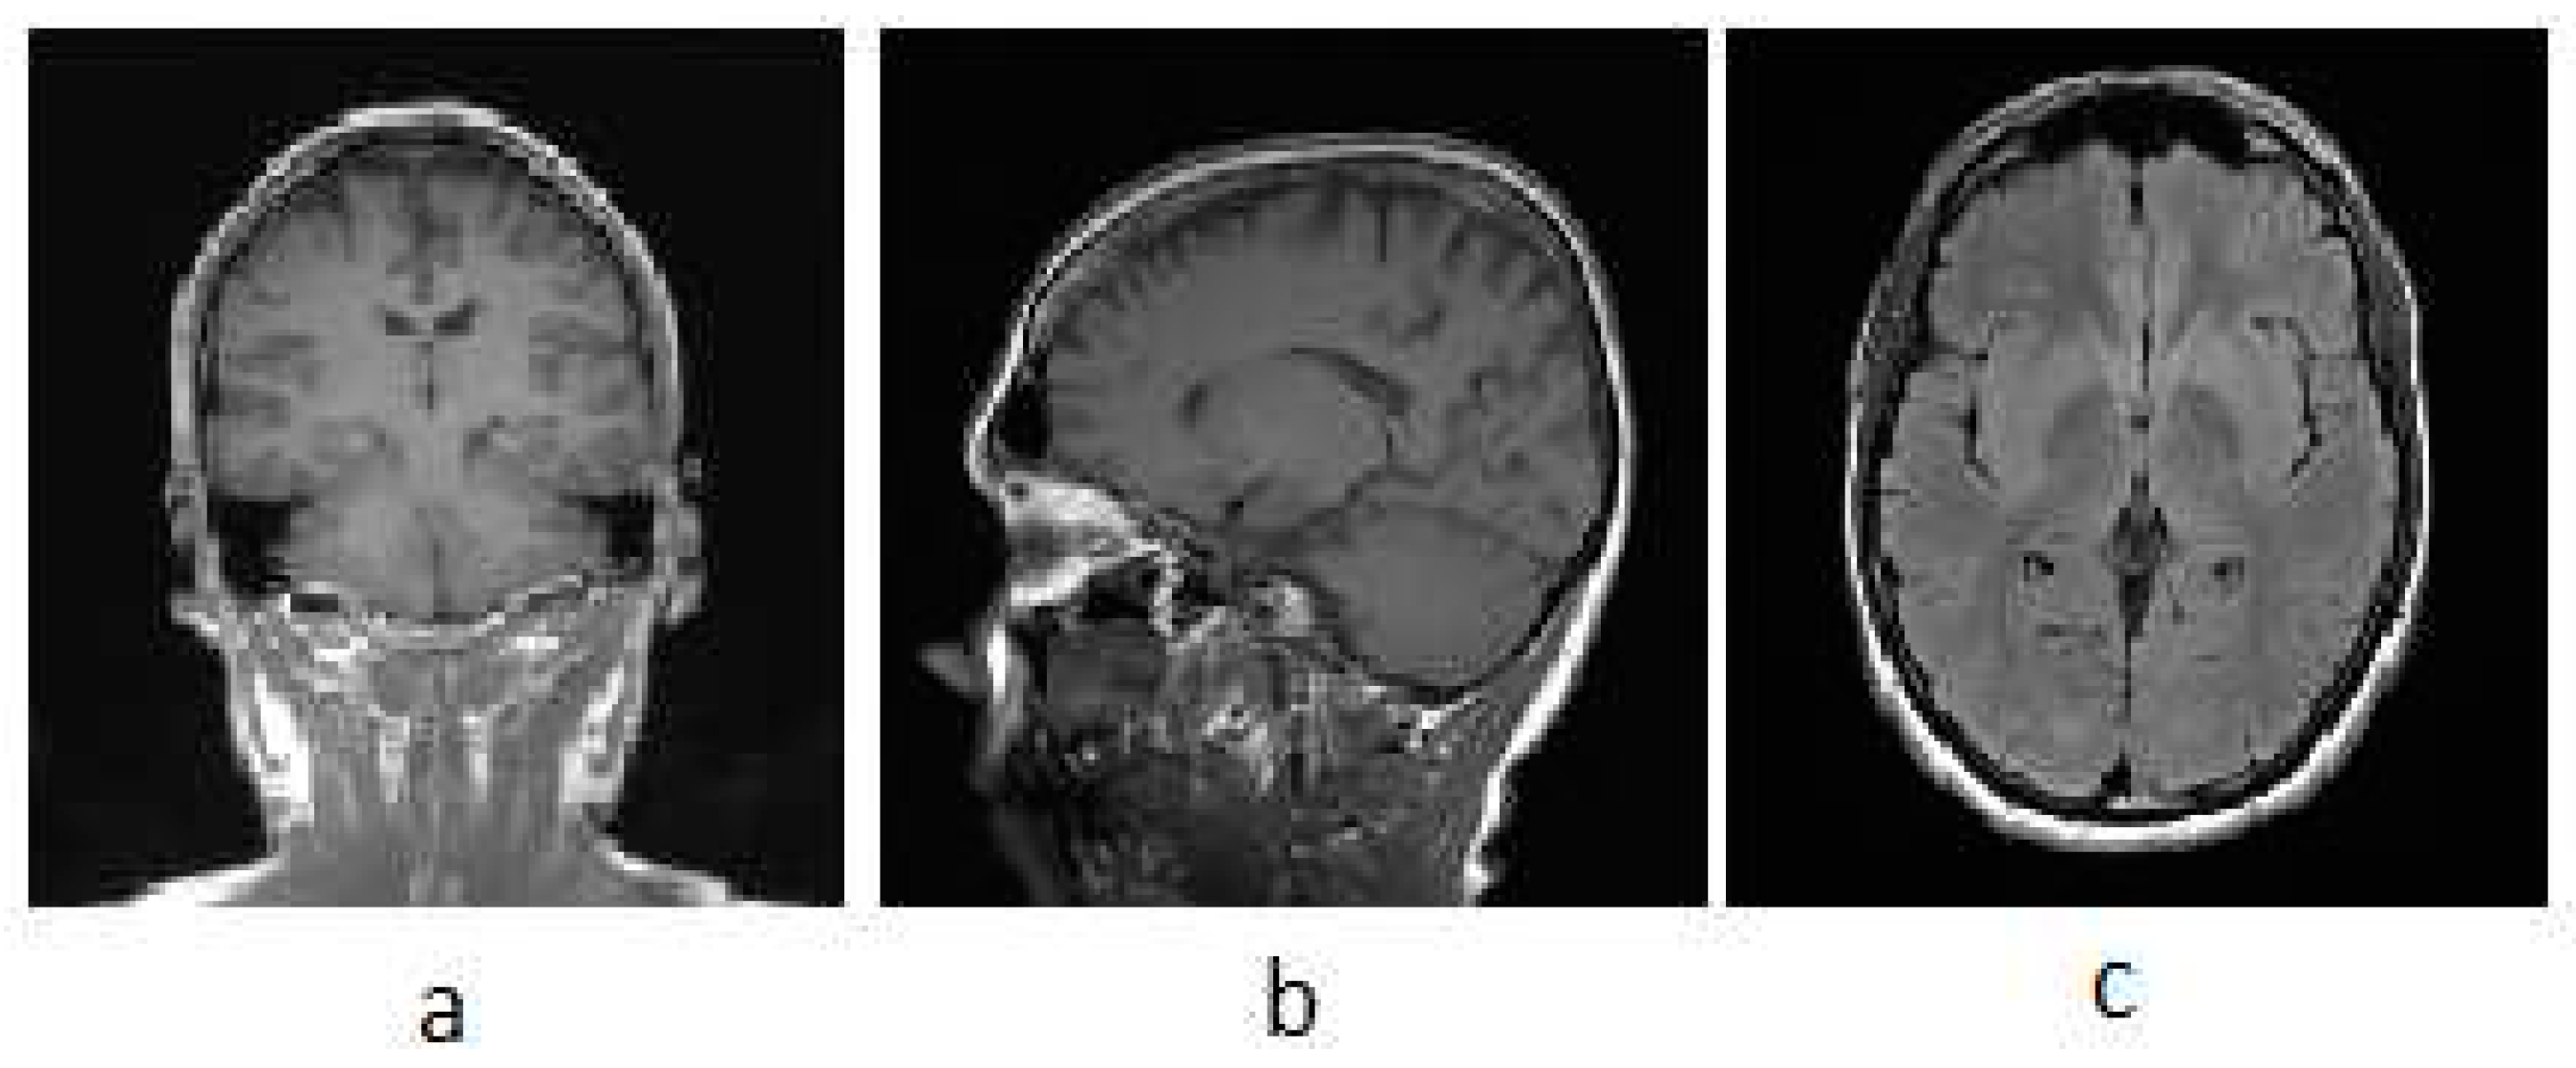

3.1. MRI